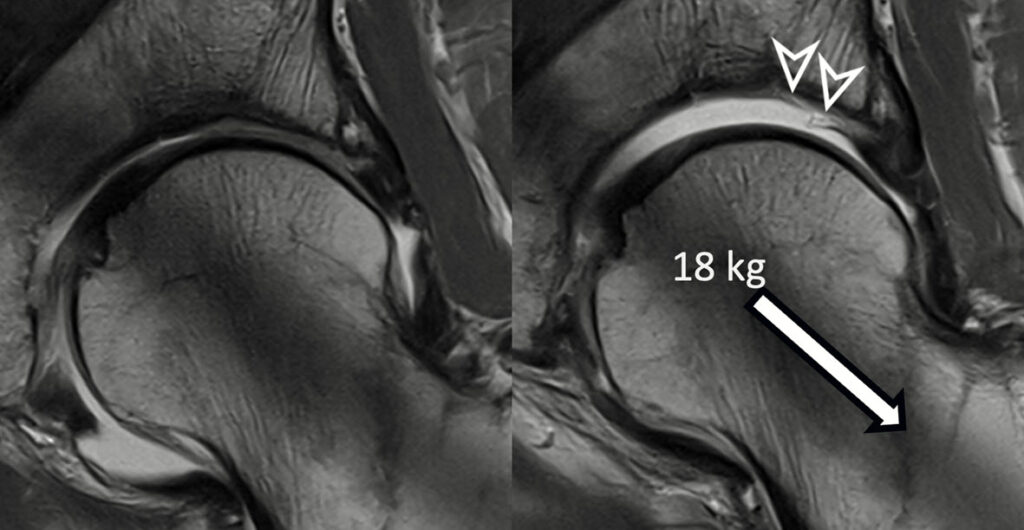

Präzise Diagnostik von Prothesen- und Schraubenlockerungen

Das MRT eignet sich besonders gut, um frühzeitig Lockerungen von Prothesen oder Schrauben zu erkennen. Es kann feinste Veränderungen an der Knochenstruktur oder an den Implantaten nachweisen, die auf eine Lockerung hinweisen könnten.

Beurteilung des umliegenden Gewebes

Neben den Implantaten erlaubt das MRT eine genaue Untersuchung der umgebenden Weichteile, wie z.B. der Abduktorenmuskulatur der Hüfte. Hier können Muskelentzündungen, Verletzungen oder Schwächen diagnostiziert werden, die Schmerzen und Funktionseinschränkungen erklären können.